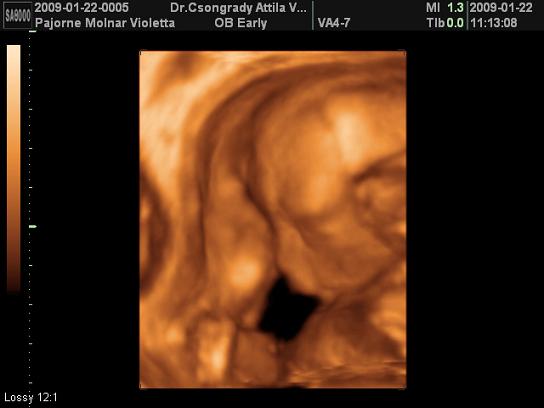

TEgnap voltam UH-n, mindjárt mutatok képet. Sajna Levente elég rossz néven vette, hogy zargatjuk, ahogy tudta takarta magát. Így nem sokat láttunk belőle, de azt megosztom Veletek.

Vivi, még csak most jelentetted be, hogy kisbabát vársz és már félidőnél tartasz. Nem semmi. Szépséges Levente, milyen szépen megmutatta magát! Nagyon klassz felvételek.